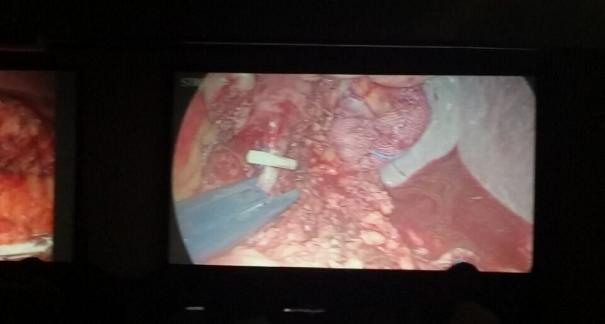

2015年10月23-25日,河北省醫(yī)學(xué)會肝膽外科學(xué)術(shù)年會在河北省石家莊市頤園賓館隆重召開。本次學(xué)術(shù)會議河北省醫(yī)學(xué)會特邀了北京301總院的胡明根教授、天津第一中心醫(yī)院的張雅敏教授、山西醫(yī)大醫(yī)院的趙浩亮、河北醫(yī)科大學(xué)第二醫(yī)院劉建華教授等國內(nèi)知名專家參會。參加會議的醫(yī)院達100余家,近300名肝膽外科的臨床專家和一線醫(yī)生們親臨會場,在此進行廣泛的學(xué)術(shù)交流。25號全天會議安排了五臺手術(shù)視頻演示,全體參會人員進行觀摩,并實時提問,進行手術(shù)交流。演示手術(shù)包括腹腔鏡胰、十二指腸切除術(shù)、腹腔鏡左、右半肝切除術(shù)、腹腔鏡門脈高壓癥的治療、兩鏡或三鏡聯(lián)合膽石癥的治療、開腹胰、十二指腸切除術(shù)、手術(shù)演示中多次使用了我公司產(chǎn)品速豐(可吸收止血結(jié)扎夾),產(chǎn)品使用滿意度受到專家們的一致好評。